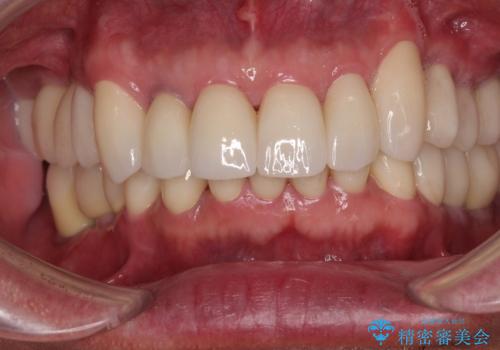

[ 虫歯・歯周病・インプラント ] 全顎補綴治療

![[ 虫歯・歯周病・インプラント ] 全顎補綴治療の症例 治療後](https://seimitsushinbi.jp/wp/wp-content/uploads/2025/08/382c499e19e22dcf6f8af5ed1cea2d03-500x350.jpg?v=1754470273)